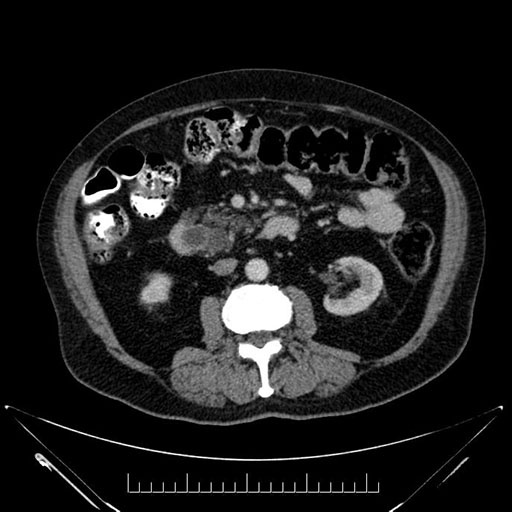

Whipple (pancreaticoduodenectomy) [case 7]

Axial - stented